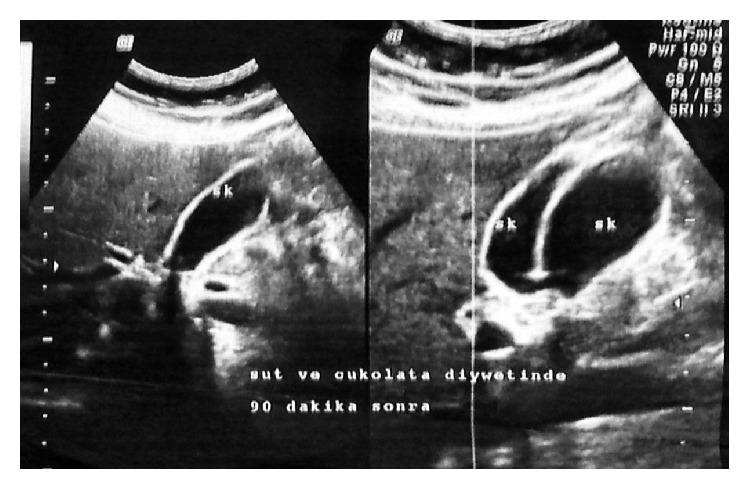

Duplication of the gallbladder is a rare congenital anomaly of the gallbladder, with an estimated prevalence of 1-3 per 3800 individuals. Unless properly diagnosed preoperatively, it can lead to biliary tract injuries and postoperative complications which may require reoperative surgeries. While previously reported cases have been treated with conventional laparoscopic cholecystectomy (LC), treatment with single incision laparoscopic surgery (SILS) has not been reported yet. We herein present the case of a 58-year-old female with gallbladder duplication who was successfully treated with SILS cholecystectomy.

胆囊重复是一种罕见的胆囊先天性异常,估计每3800人中的患病率为1 - 3例。除非术前得到正确诊断,否则可能导致胆道损伤和术后并发症,这可能需要再次手术。虽然先前报道的病例采用传统腹腔镜胆囊切除术(LC)进行治疗,但单切口腹腔镜手术(SILS)治疗尚未见报道。我们在此报告一例58岁胆囊重复的女性患者,经SILS胆囊切除术成功治疗。